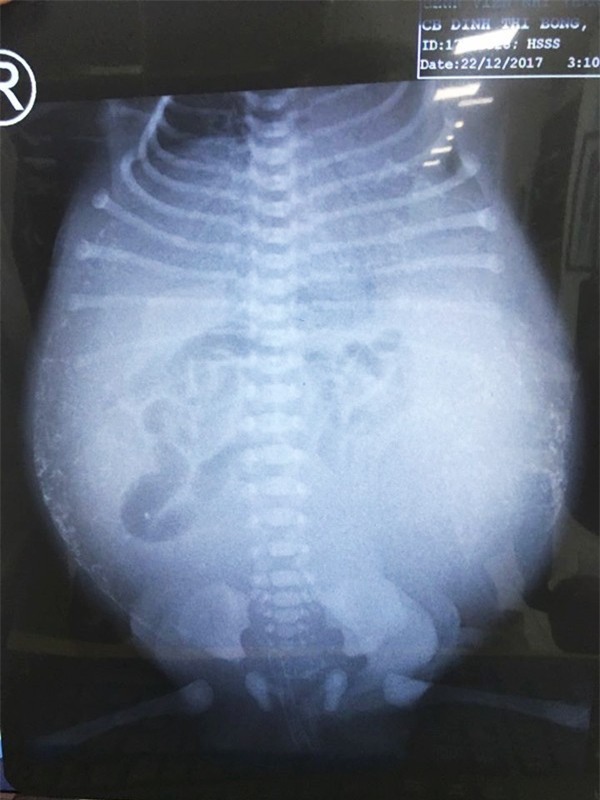

Theo lời kể của bà ngoại, bé trai con một sản phụ ở thành phố Cần Thơ được chẩn đoán theo dõi thủng ruột do viêm phúc mạc bào thai, từ trong bụng mẹ lúc thai 25 tuần. Đến tuần thứ 36, diễn tiến thai kỳ sản phụ có nhiều nước ối, lại bị tăng huyết áp nên các bác sĩ (BS) quyết định chấm dứt thai kỳ. Sau chào đời, bé bụng trướng căng, suy hô hấp, xuất huyết toàn thân, được đặt ống thở.

Khi được chuyển đến BV tuyến trên, bệnh nhi đã suy hô hấp nặng, nhiễm trùng nhiễm độc nặng, bụng bé trướng căng như quả bong bóng sắp vỡ, xuất huyết toàn thân. Thành bụng bệnh nhi nhiều nơi xuất huyết, ọc ra máu miệng, trong ống thở có bọt máu. Trước bệnh nguy kịch này, các BS thăm khám xong đều lắc đầu, giải thích với gia đình rằng tiên lượng bé rất khó qua khỏi.

Sau 2 ngày hồi sức tích cực, đặt ống dẫn lưu ổ bụng tạm thời, ca phẫu thuật được tiến hành. Trước tình trạng bụng bệnh nhi đầy dịch phân, mủ, thủng ruột non, viêm toàn bộ ổ bụng ekip mổ phải đưa tạm một lỗ ruột ra ngoài để giải áp chứ không nối ruột ngay được.